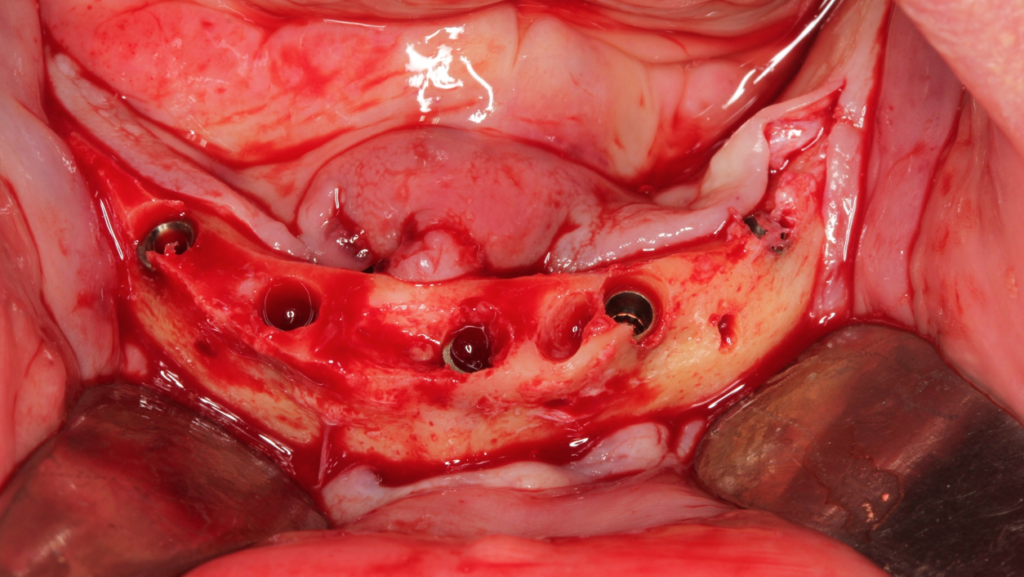

Paciente do sexo feminino, 82 anos, com a presença de dentes anteriores de mandíbula usando prótese móvel na região posterior por mais de 30 anos. Com isso, a reabsorção óssea posterior causou um desnível muito grande em relação à região anterior.

Através do programa Blue Sky (em parceria com a empresa Odontoplanning), foi feito planejamento guiado com 2 guias. O primeiro guia de recorte ósseo, tem como objetivo o recorte e aplainamento ósseo, deixando uma altura óssea mais uniforme entre a região posterior e anterior da mandíbula.

Através da imagem do osso recortado é planejada a guia de perfuração que vai se encaixar de uma maneira perfeita no osso recortado.

Lembrando que essas guias serão apoiadas exclusivamente no osso, sem envolvimento de mucosa, portanto há que se fazer incisão e descolamento mucoperiostal suficiente para o encaixe da guia.